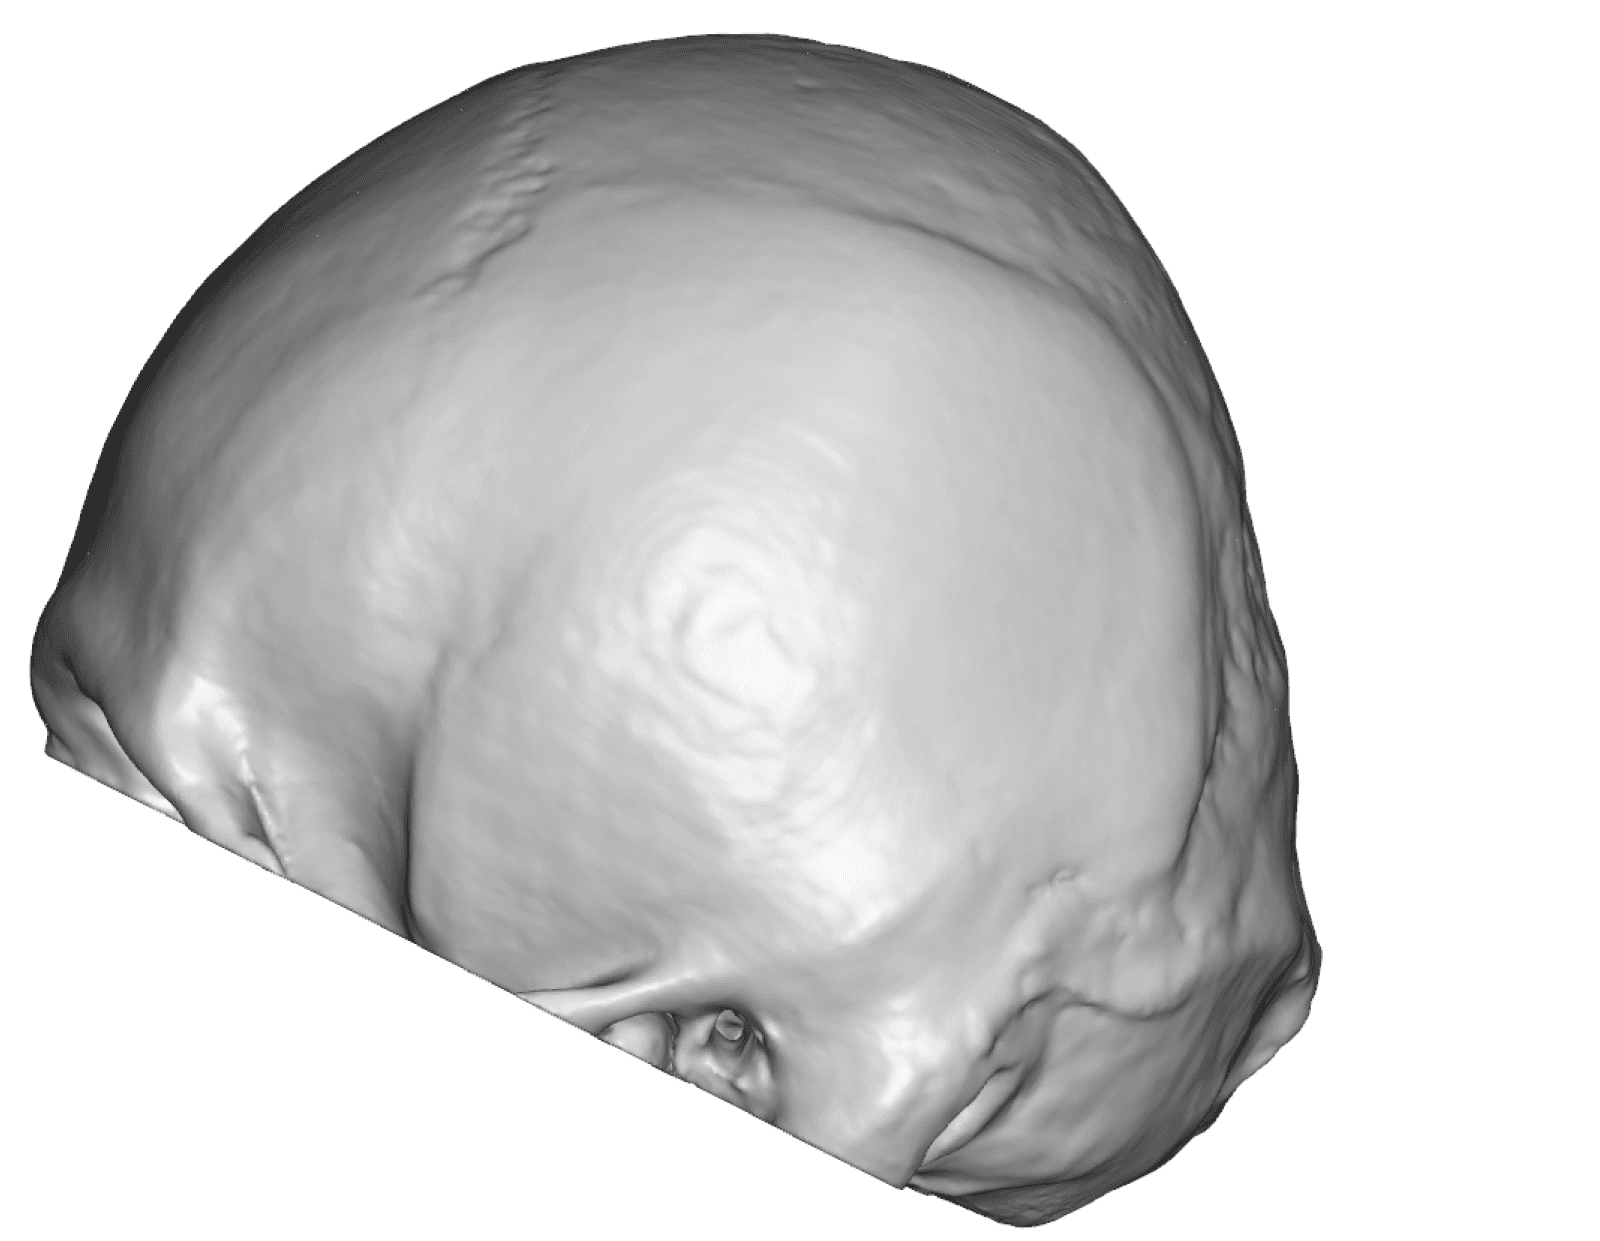

Severe narrowing skull deformity from prior sagittal craniosynostosis repair as an adult.

Complete replacement of entire skull by a custom implant with temporal fat injections.

Severe narrowing skull deformity from prior sagittal craniosynostosis repair as an adult.

Complete replacement of entire skull by a custom implant with temporal fat injections.